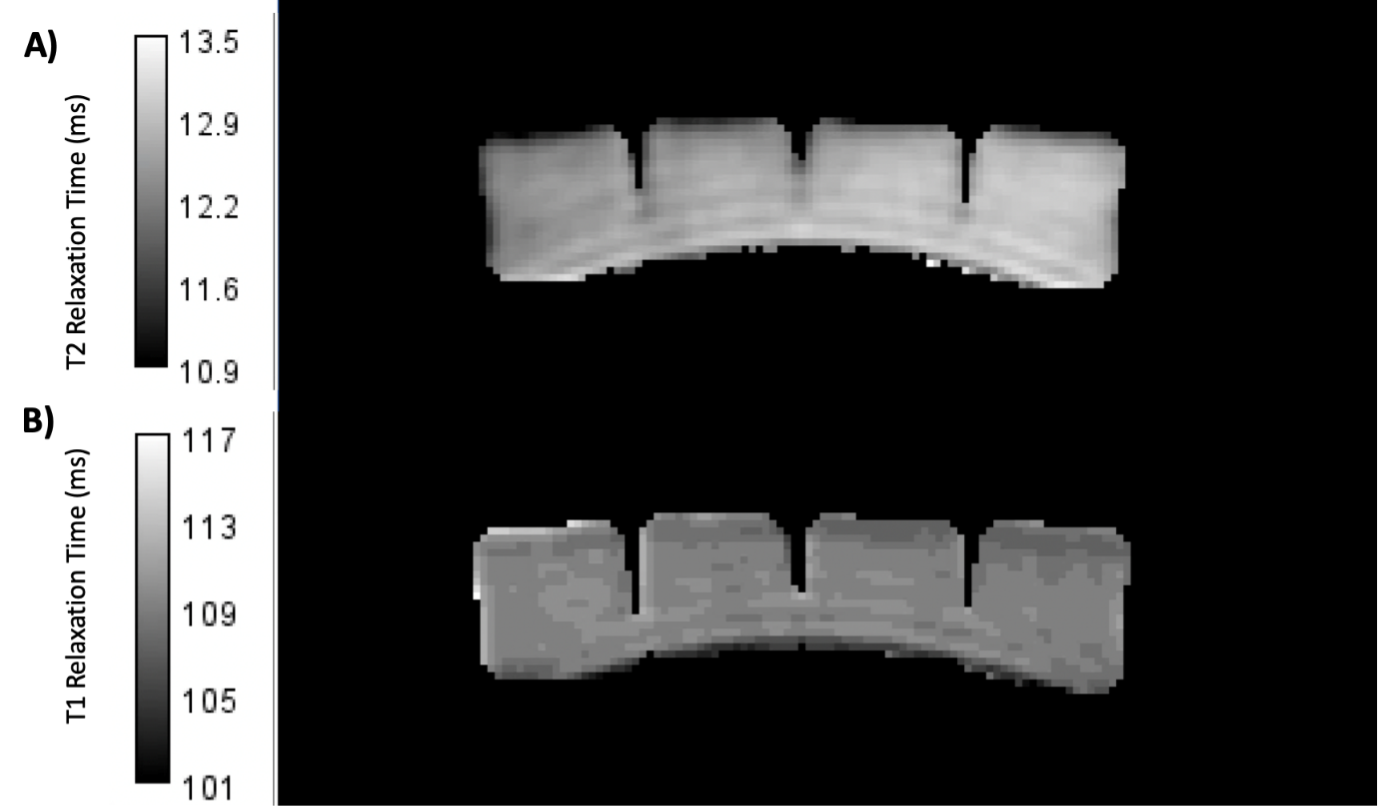

2D inversion recovery images were acquired using inversion times (TI): 50, 60, 75, 100, 200, 250, and 500 ms. T2 was characterised using a spin echo sequence with echo times (TE): 10, 15, 20, 40, 60, and 80 ms. The following imaging parameters were used for all relaxation data acquired: Number of slices=1, acquisition matrix size = 128 x 128, reconstructed matrix size= 256 x 256, slice thickness = 5 mm, field of view (FOV) = 256 mm, and bandwidth= 122 Hz/pixel. MTR values were calculated using an Enhanced Fast Gradient Echo 3D sequence (EFGRE3D) with and without a fermi magnetization transfer pulse of duration 8 ms, offset by 1200 Hz, and a flip angle of 200°. The imaging parameters of the EFGRE3D sequence were: number of slices = 86, slice thickness = 2 mm, FOV = 256 mm, acquisition matrix size = 320 x 320, bandwidth = 244 Hz/Pixel, TI = 32 ms, and TE = 2.77 ms.Voxel-wise curve fitting was performed on the resultant relaxation data to allow the creation of T1 and T2 maps respectively of the phantom in MATLAB (2022a, MathWorks, Cambridge, MA), displayed in Figure 2. Equations 1 and 2 were used for fitting the T1 and T2 data respectively, where Mxy is the signal intensity at each voxel location, and M0 is the maximum signal. MTR values for the phantom were calculated using Equation 3, where SIMTon and SIMToff are the signal intensities with the magnetization pulse turned on and off respectively.

Figure 2 - T2 (A) and T1 (B) maps generated for a block of store-bought jelly